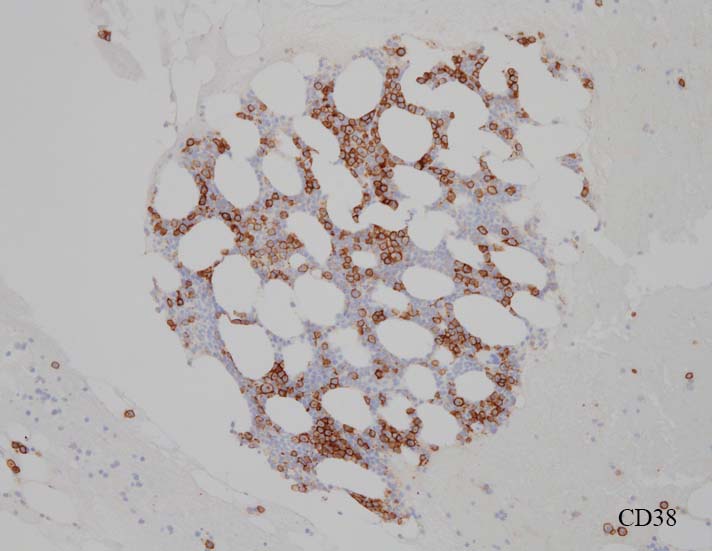

免疫染色

blastic cellsは, CD45+, CD34+, CD38+, TdT+, CD7+, HLA-DR+, CD123+. cCD3-, sCD3-(FCM), CD20-, CD19-とCD79a-(?) (plasma cellが陽性でIHCでは判定が難しい), MPO-.

CD34, CD38陽性細胞の多くは, CD123+, HLA-DR+ .

CD3-, CD79aは増加しているplasma cellsが陽性で判定が難しい. CD10-, MPO-. (CD10は画像欠)